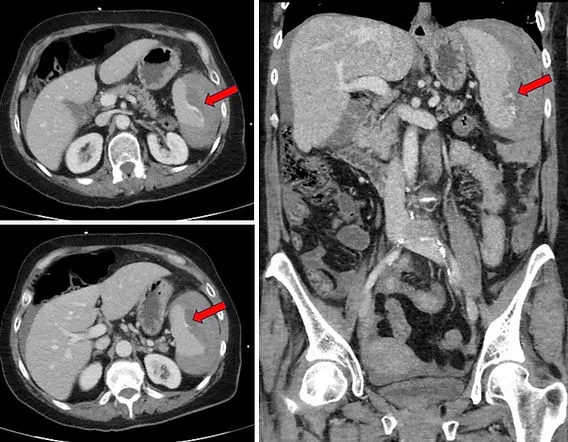

CT Scan with IV Contrast: Gold standard for hemodynamically stable patients. Accurately identifies specific organ injury, retroperitoneal hemorrhage, and quantifies bleeding.

- Angioembolization: A key adjunct to NOM for patients with active arterial extravasation on CT scan but who are otherwise stable.